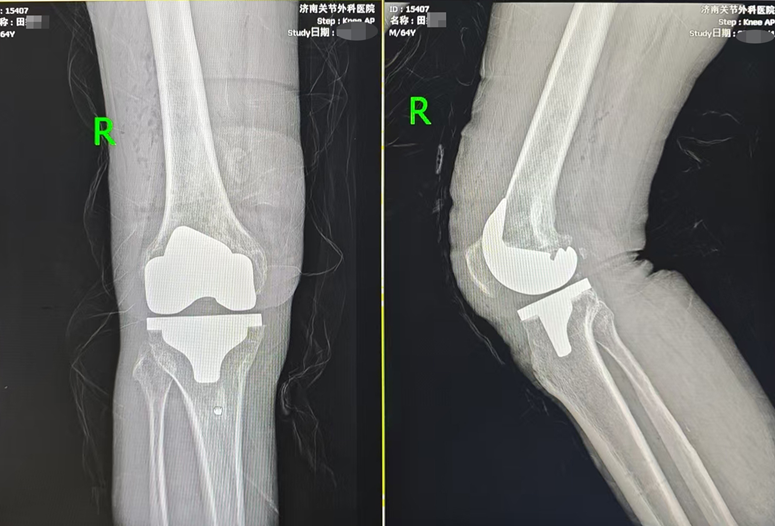

在亲戚的推荐下,田大爷慕名来到济南关节外科医院。入院后,医护团队为田大爷进行了全面、细致的检查,明确其符合膝关节置换手术指征。结合田大爷的年龄、身体状况及康复需求,医院手术团队反复研讨,为其定制了Mako智慧机器人辅助全膝关节置换的手术方案,并顺利完成手术。

相较于传统手术,机器人辅助关节置换手术更加精准、更加微创。手术前,机器人依托患者的检查报告,构建出贴合其骨骼解剖结构的3D模型,精准规划手术路径与操作细节;术中,机器人实时监测手术进程,通过毫米级精准计算,辅助医生完成截骨、假体安放等关键操作,精准度精确至0.1毫米,最大限度减少对周围组织的损伤,为术后快速康复奠定了坚实基础。

手术成功后,医院采用快速康复理念结合责任制整体护理模式,为田大爷制定了个性化康复计划,医护人员全程贴心指导、细致照料,术后不到24小时,田大爷便成功下地行走。家属由衷感叹道:“专科医院就是专业,技术好、服务暖,没让我们失望!”